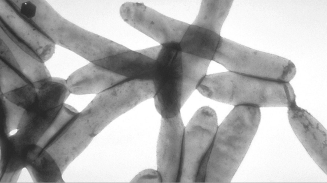

New York City Legionnaire's Disease Outbreak, Symptoms and Treatment: Outbreak kills 10 in Bronx, 100 Infected

New York City is in the brink of a major Legionnaires' disease as ten people have been killed and more than a hundred people affected, the city health department announced.